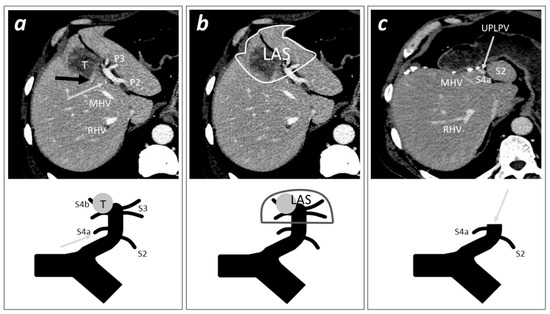

Figure 2. A case of tumor invading the distal part of the UPLPV treated with Left Anterior Sectorectomy. The careful pre-operative evaluation of CT-scan is fundamental to identify the pattern of LPV’s branching, to ascertain the presence of LAS, and to indicate the surgical procedure of left anterior sectorectomy. Each picture (“a”, ”b”, and “c”) includes a CT-scan imaging (above) and a schematic illustration of the portal skeleton (below) of the pre- or post-operative hepatic portal anatomy of a patient with a tumor invading the distal part of the UPLPV and the right horn of the LPV. (a) (Pre-operative) the CT-scan shows a portal pedicle represented by one branch for S2 (P2); a portal pedicle with two branches for S3 (P3); a portal pedicle originating from the right horn, including one branch for S4b (not visible, completely invaded by the tumor) and one branch for S4a invaded by the tumor at its origin (black arrow); and an independent portal pedicle for S4a originating from the UPLPV (grey arrow). (b) (Pre-operative) The patient can be classified as pattern I of LPV’s branching (presence of at least one independent portal pedicle for each of S2, S3, S4a, and S4b) [7]; the delimitation of the LAS, including the distal part of the UPLPV, the right and left horns, S3, and S4b; when planning a left anterior sectorectomy, the section of the UPLPV must be planned with the goal to remove the distal branching (left and right horns) and to spare the portal pedicles for the posterior segments (S2 and S4a), with particular attention to the origin of proximal independent portal pedicles for S4a. (c) (Post-operative) After the left anterior sectorectomy, the grey arrow indicates the stump of the LPV sectioned. (T, tumor; P2, portal pedicle for segment 2; P3, portal pedicle for segment 3; MHV, middle hepatic vein; RHV, right hepatic vein; S2, segment 2; S3, segment 3; S4a, segment 4 superior; S4b, segment 4 inferior; LAS, left anterior sector; UPLPV, umbilical portion of the left portal vein).

The surgical treatment of tumors invading the distal part of the umbilical portion of the left portal vein (UPLPV) may represent a challenge for liver surgeons (Figure 1a). The presence of tumors with certain or suspected invasion of the UPLPV, when suitable for surgery, requires a radical anatomical liver resection with removal of the tumor, the invaded vessel, and the portion of parenchima supplied by that vessel; the traditional radical surgical approach in such cases is represented by a major resection, the left hemi-hepatectomy (Figure 1b).

With the aim to identify alternative and more conservative surgical procedures for the treatment of patients with tumors invading the UPLPV, we recently performed an anatomo/radiological study and introduced the novel anatomical concept of left anterior sector (LAS), an independent anatomo/functional unit corresponding to the anterior portion of the left hemiliver, including segment 3 (S3) and S4 inferior (S4b), and supplied by an independent sectorial portal pedicle (PP) represented by the distal part of the UPLPV downstream from the origin of independent PPs for left posterior segments (S2 and S4a) [7] (Figure 1c). The definition of this new anatomical entity assumed that S4 should be divided into two separated sub-segments; this was based on the finding that, in 79.5% of patients, S4a and S4b are supplied by independent portal pedicles (PPs) and should be considered two separated anatomo-functional units [7].

The identification of the pattern of LPV’s branching was fundamental in order to radiologically define the presence of LAS (typically present in pattern I patients but identifiable even in patterns II and III patients, overall present to 98% of cases) and to define the adequate level of section of the sectorial PP of the LAS represented by the UPLPV [7] (Figure 2).